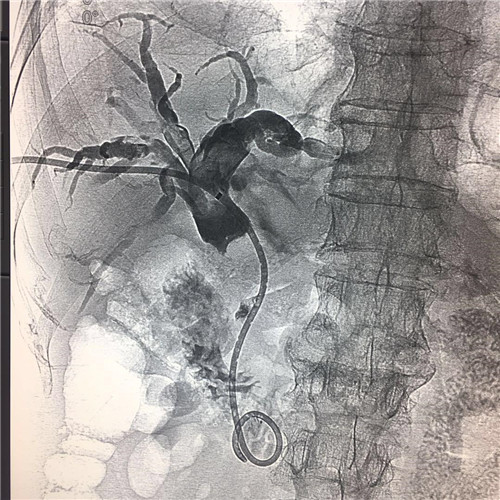

患者全身皮肤金黄瘙痒难忍,在B超定位下行肝内胆管引流术、术后因引流不畅拔管;在胃镜下逆行ERCP胆管支架植入术,经过术者反复操作,但导丝无法通过病变段。看到患者痛苦不堪,家属迫切治疗的场面,介入科李建国主任现场会诊提出为患者在介入下行PTCD治疗的意见。术前经过讨论制定多套严密方案,与患者及家属多方沟通达成介入手术共识;术中精准定位穿刺选择不同的导丝、导管多角度旋转闭塞原地不动,时间一分一分过去......在医护人员努力下,闭塞的胆道开通了,再经球囊分段扩张病变狭窄段,内外引流管放置顺利300余毫升的黑褐色胆汁流出......

在护理人员精心的配合下,手术历时30余分钟圆满成功,彻底解决了患者梗阻性黄疸引发的皮肤黄染,保护了肝功能。

顺行开通高位胆管梗阻性黄胆经皮肝穿胆管引流术优势明显